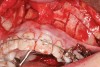

Figure 2b  A corticotomy in SFOT is a surgical technique in which only the cortical bone is cut, perforated, or mechanically altered to the depth of the medullary bone and the medullary bone remains intact.

Figure 2b

Figure 3  A corticotomy in SFOT is a surgical technique in which only the cortical bone is cut, perforated, or mechanically altered to the depth of the medullary bone and the medullary bone remains intact.

Figure 3